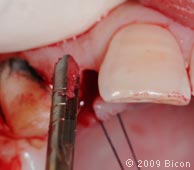

5. Ретракционные швы, удерживающие два небных лоскута.